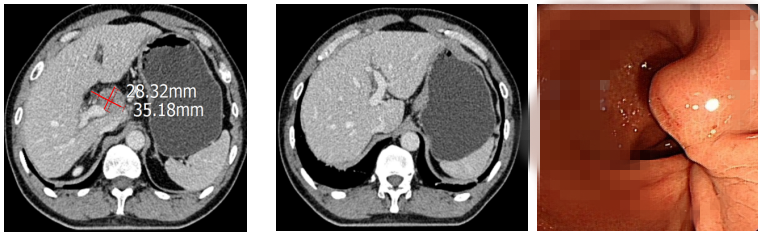

王慧娟主任医师组织科室讨论详细分析了文某的病情,与患者及家属充分沟通后,于2021年10月—2022年2月行一线6周期姑息性化疗。每两周期复查提示病情评估为稳定(病灶缩小但达不到部分缓解),患者症状较前缓解。2022年3月患者出现左侧颈部淋巴结增大(4cm),评估病情后提示病情进展,行颈部淋巴结穿刺活检,病理结果及PD-L1检测示:(淋巴结)转移性腺癌,PDL1(sp263)TPS<1%,CPS<1%,Her-2阴性。再次与患者及家属沟通后,调整为免疫检查点抑制剂联合二线全身静脉化疗6周期。1周期治疗后患者颈部淋巴结明显减小。2周期后影响评估:部分缓解(PR)。此后患者每3周予以免疫检查点抑制剂维持治疗,直至目前,患者已免疫治疗1年,2023年4月复查CT、胃镜提示颈部淋巴结、胃窦溃疡、肝转移病灶几近消失,病情依然稳定。目前患者已安全度过18月余,我院化疗科会继续随访此患者,同时希望更多朋友保持健康的饮食规律,定期体检,早发现、早诊断、早治疗。

二线6周期化疗后腹部CT及胃镜